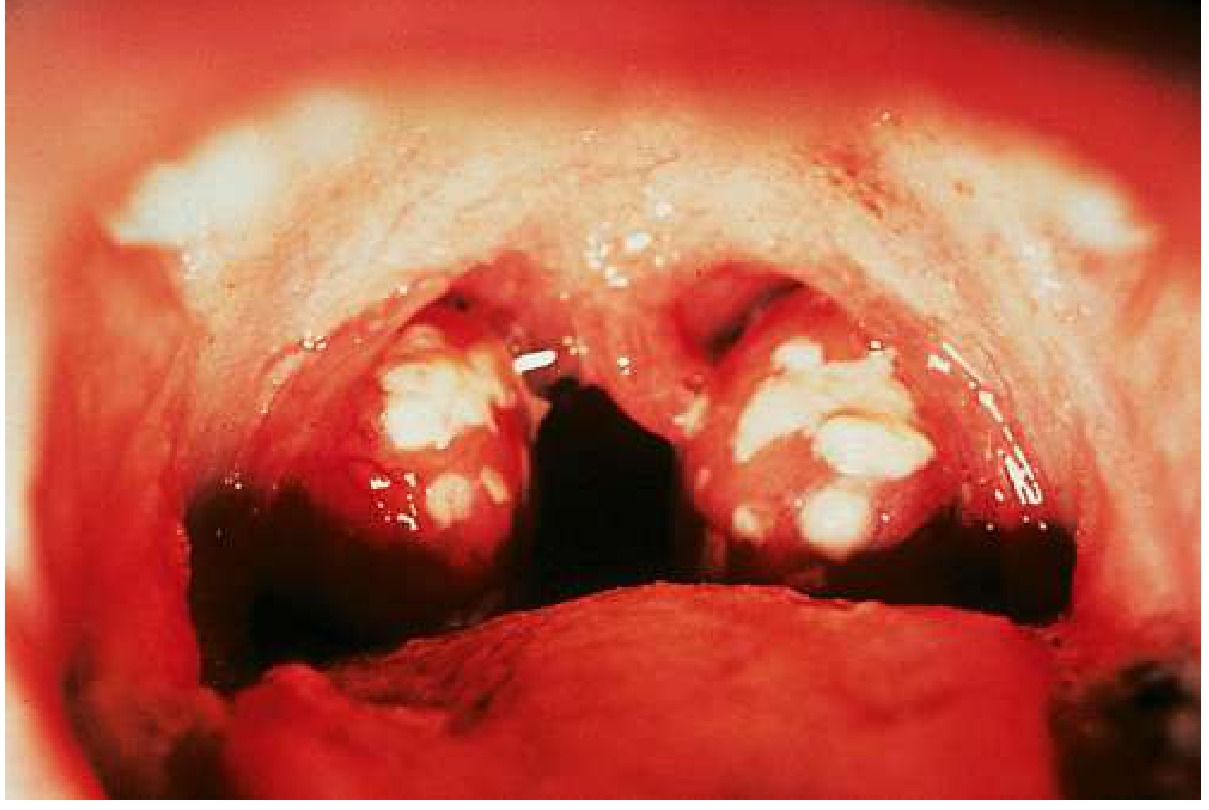

Exudative streptococcal pharyngitis with tonsillar hypertrophy and white-yellow exudates

Acute exudative streptococcal pharyngitis: erythematous, hypertrophied tonsils with confluent white-yellow exudate. — Goldman-Cecil Medicine